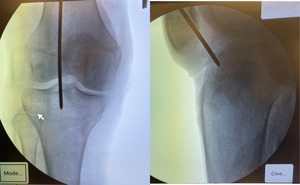

After Institutional Review Board exemption, three paired (6 total) fresh-frozen adult cadaveric lower extremities with intact knee joints were included in the study. With each cadaveric extremity in the semi-extended position, an extra-articular, lateral parapatellar approach was utilized for IMN placement of an unfractured tibia. First, a bump was placed under the ipsilateral hip, then the knee was flexed to 20° and stabilized such that the tibia was parallel to the floor, simulating semi-extended positioning. A lateral parapatellar incision was made through the skin, and meticulous dissection of the retinaculum and surrounding tissue was performed to reveal the proximal tibia per the technique described by Kubiak et al.63 A short Kirschner wire (K-wire) was then inserted deep to the patellar tendon and superficial to the synovium and advanced to the tibial tubercle. The intended entry position was slightly lateral to the center of the tibial tubercle. The K-wire was drilled into the tibia, and fluoroscopic anteroposterior (AP) and lateral imaging of the knee was used to confirm the correct entry position (Figure 1). An opening cannulated reamer was placed over the K-wire to open the canal. The K-wire and reamer were removed, and a long ball-tipped guidewire was inserted and advanced to the most distal aspect of the tibia as confirmed by fluoroscopy. The length of the tibia measured by the guidewire was recorded for nail selection. Next, the intramedullary canal of the tibia was initially reamed with a flexible 9 mm reamer, then in increasing 0.5 mm increments until the appropriate diameter was reached. A Stryker T2 Alpha Nail (Stryker Ltd, Kalamazoo, MI) of appropriate diameter and length was placed into the tibia with fluoroscopic imaging confirming successful positioning (Figure 2).